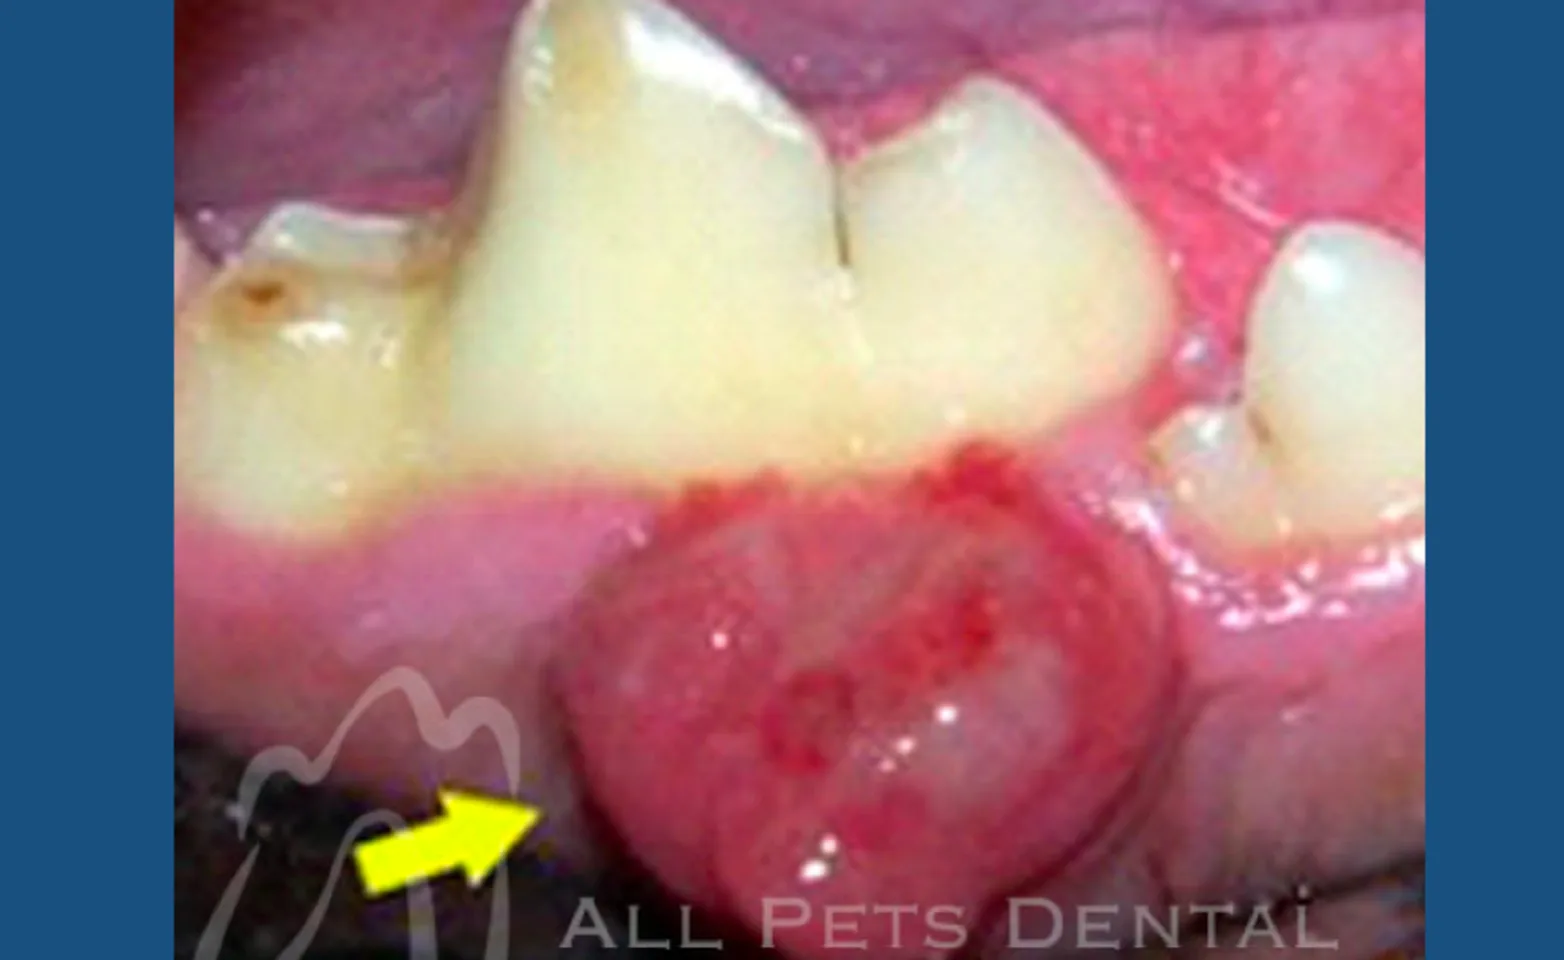

Peripheral Odontogentic Fibroma (POF)

Peripheral odontogenic fibromas include fibromatous and ossifying epulides. Epulis (plural=epulides) is a general term referring to a gingival mass of any type. The ossifying type is distinguished from the fibromatous type by containing varying amounts of bone, osteoid, dentinoid, or cementum-like tissue. Peripheral odontogenic fibromas are considered benign. Complete surgical removal is the treatment of choice.